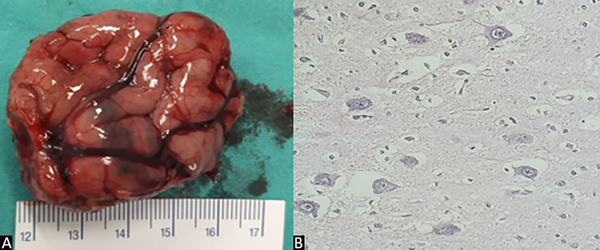

El informe anatomopatológico arrojó el resultado de displasia cortical focal tipo IIb de Taylor (Figura 5).

Figura 5. Caso 1. A) Exéresis de lesión de 4.5 cm de largo. B) Preparado de anatomía patológica: alteración de la laminación cortical, neuronas dismórficas y gigantes, células en balón, núcleos grandes y múltiples.